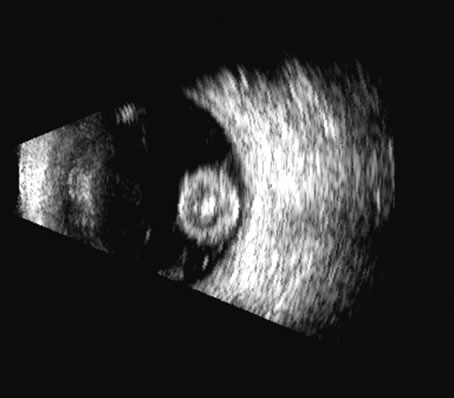

Fig. 24. In this traumatized eye, the crystalline lens was completely dislocated and can be seen as a rounded mass in the posterior chamber, in a suitable plane.

On B-scan, the invasion or replacement of the choroid by tumor is of diagnostic importance. Subretinal hemorrhage rests on a smooth curve of the posterior poles; whereas melanoma may replace the choroid, producing an “excavated” pattern.36 A completely dislocated lens can also emulate a tumor but can be differentiated by clinical findings and by having the patient move his or her eye during the examination, which causes lens displacement (Fig. 24).